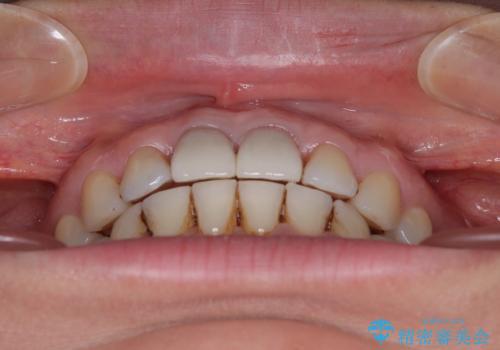

隙間をセラミックで閉じたら不格好で歯肉から出血 矯正治療と歯周外科で綺麗な前歯に

- 隙間の空いた前歯をセラミッククラウンで補隙したところ、歯肉から出血してしまい、何とかしたいとのことで来院された患者様です。

初めは前歯のみの処置で改善を希望されていたため、広範囲に処置範囲を広げることで歯の幅がバランスする治療を提案しましたが、削らなければならない歯が増えてしまうため、患者様と相談して全顎矯正により前歯のスペースを閉じていくこととしました。

不適合なクラウンが装着されていたため、歯周ポケットが深くなっていましたので、矯正治療前に歯周外科処置を行って歯周ポケットを除去し、矯正治療後にオールセラミッククラウンにて補綴治療を行うこととしました。

前歯の見た目はもちろん、出血や腫脹のない健全な前歯の状態を獲得することができました。